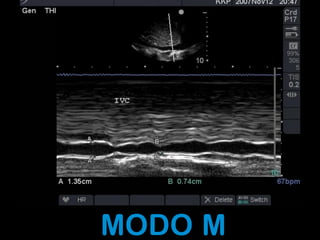

MODO M